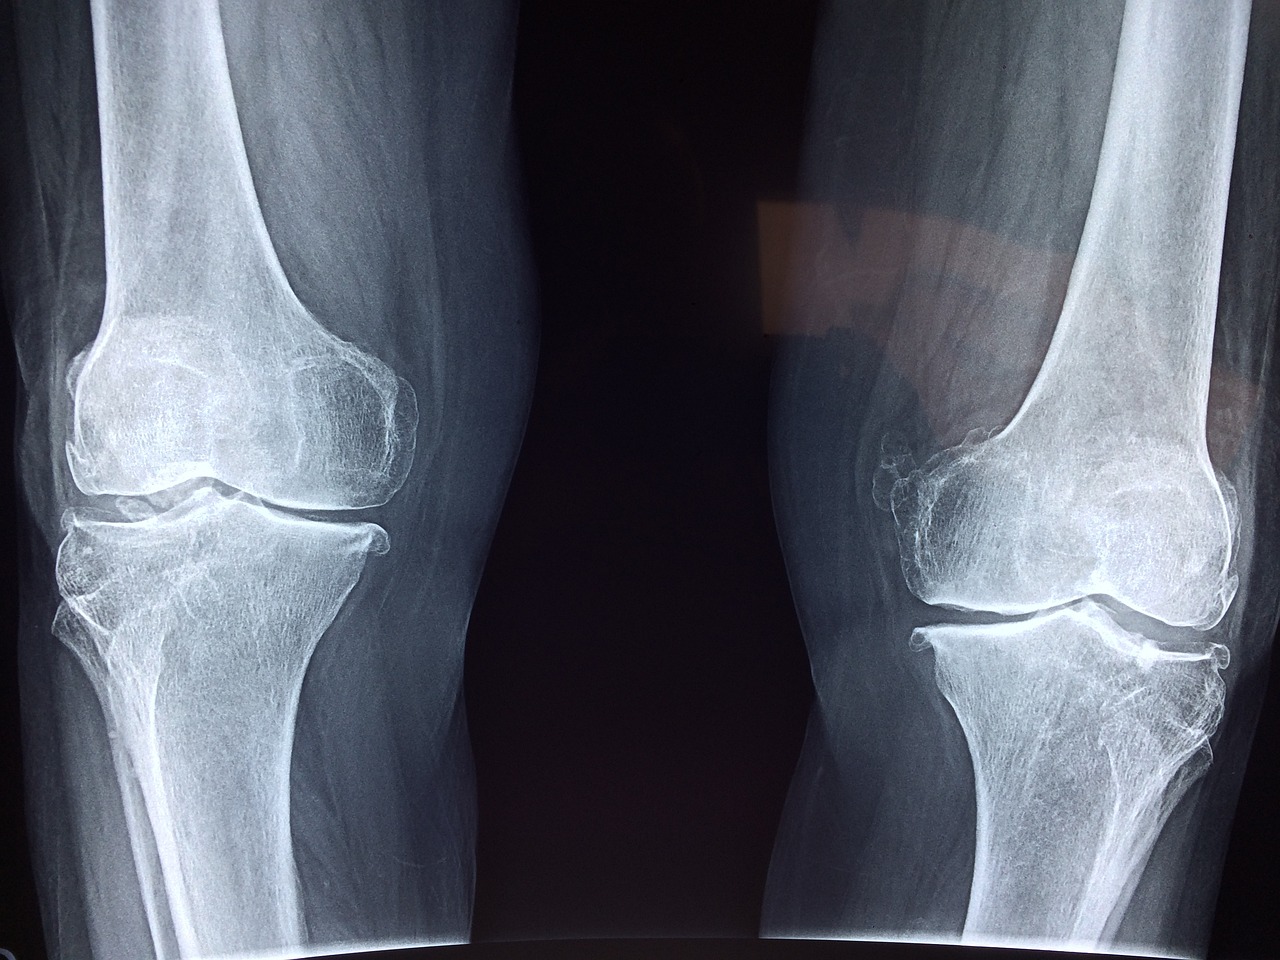

W wyspecjalizowanym ośrodku medycyny regeneracyjnej SPORT-MED, dr Jan Paradowski wykorzystuje komórki macierzyste zamiast lub w połączeniu z procedurą operacyjną, w leczeniu urazów sportowych i stanów związanych ze starzeniem i degeneracją: kolana, biodra, barku, kręgosłupa, stopy i stawu skokowego oraz innych stawów. Nasza autologiczna Terapia Komórkami Macierzystymi wykorzystuje dorosłe mezenchymalne, multipotencjalne komórki macierzyste pobrane z pacjenta własnego szpiku kostnego, które następnie zostają z powrotem wstrzyknięte u tego samego pacjenta w kontuzjowane, uszkodzone lub bolesne miejsce. Medycyna regeneracyjna oferuje bardzo szerokie możliwości leczenia wielu schorzeń dotyczących różnych struktur organizmu.

Niestety liczba komórek macierzystych u ludzi zmniejsza się wkrótce po narodzinach. To ograniczenie tłumaczy, dlaczego nasz organizm zużywa się i pogarsza się nasz stan wraz z wiekiem – im mniej komórek macierzystych, tym mniejsza zdolność do samonaprawy i zastępowania zużytych komórek. Naszym celem w Terapii Komórkami Macierzystymi jest pobranie ich z jednej okolicy ciała pacjenta, w której występują w większym stężeniu i wstrzyknięcie ich do uszkodzonego stawu, aby potencjalnie zwiększyć możliwości regeneracyjne komórek macierzystych.

Komórki macierzyste wykorzystywane przez nas w ortopedii, mogą stworzyć zdrową tkankę, zastępując uszkodzoną i potencjalnie pomóc organizmowi w samonaprawie. Dla przykładu, komórki macierzyste wstrzyknięte w rejon zniszczonej kości, mogą zróżnicować się w komórki kostne i pomagają w gojeniu uszkodzenia.